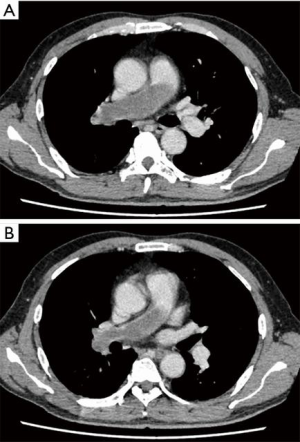

A 58-year-old man was referred to our hospital with a fever and dyspnea on exertion. Enhanced computed tomography showed low-attenuation filling defects occupying the entire luminal diameter of the right main PA, peripherally extending into the right interlobar PA (Figure 1). Positron emission tomography demonstrated an intense uptake of florine-18 fluorodeoxyglucose in the intraluminal defects, with a maximum standardized uptake value of 15.2 (Figure 2). A pulmonary angiogram showed severe stenosis of the right main PA (Figure 3). Right heart catheterization revealed a severely elevated systolic right ventricular pressure of 76 mmHg. Pulmonary function tests showed a mild restrictive ventilatory disorder with vital capacity of 3.05 L (79.6% of predicted value) and forced expiratory volume in 1 second of 2.20 L (70.1% of predicted value). The patient’s condition rapidly deteriorated and he became bed-bound. Based on these findings, PA sarcoma was clinically suspected, and the initial surgical strategy consisted of pulmonary endarterectomy and right pneumonectomy, followed by reimplantation of the right lower lobe in order to preserve the post-operative pulmonary function. All procedures performed in this study were in accordance with the Helsinki Declaration (as revised in 2013). Informed consent was obtained from the patient for publication of this manuscript and any accompanying images.